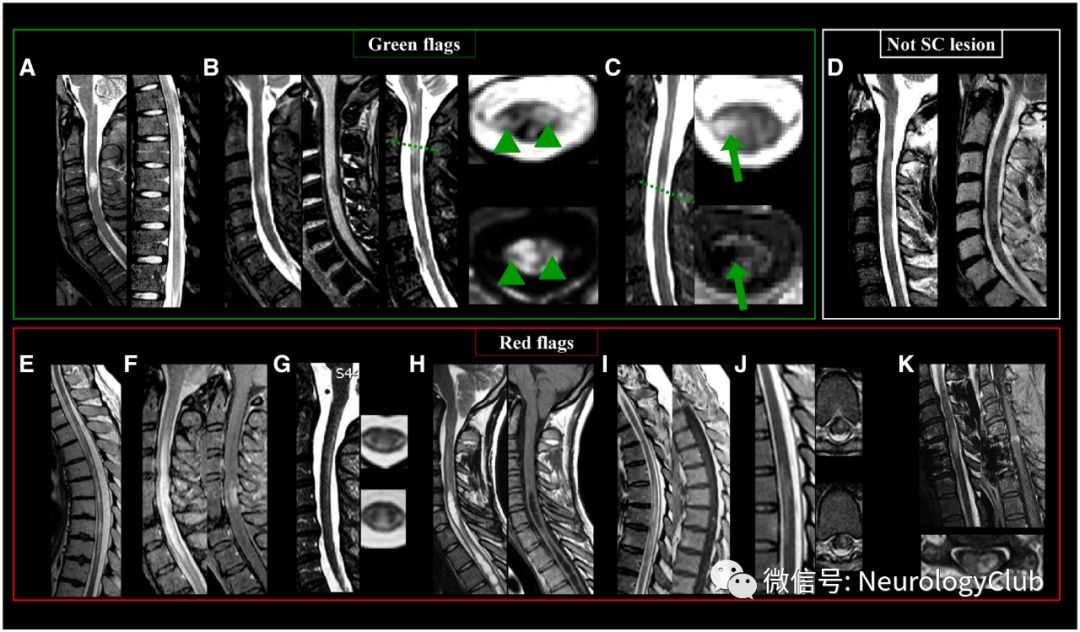

图4:MS患者脊髓典型和非典型病灶以及不应该计数在内的病灶;左上:绿旗征:(A)矢状位短时间反转恢复序列上颈、胸髓病灶;(B)3T-T1WI上可见颈髓低信号(绿箭头);(C)T2WI和相位敏感 反转恢复序列可见颈髓病灶累及侧柱和中央灰质(绿箭);右上:(D)弥漫性脊髓病变,边界不清,不符合脊髓病灶的定义;底部:红旗征:(E)见于NMOSD的纵向广泛性脊髓受累,病灶范围在3个节段以上;(F)见于神经结节病的纵向广泛性脊髓受累,病灶范围在3个节段以上,伴软脊膜和脊髓周围强化;(G)见于亚急性联合变性的广泛选择性侧柱和后柱受累;(H)脊髓空洞;(I)见于动静脉瘘的广泛性T2高信号病灶,从脊髓圆锥前部延伸,可见斑点状和扭曲强化;(J)见于亚急性缺血性脊髓病的胸髓前部高信号病灶,延伸累及两个以上椎体节段;(K)脊髓型颈椎病患者颈髓T2高信号病灶,可见“薄煎饼样”强化;SC=脊髓。